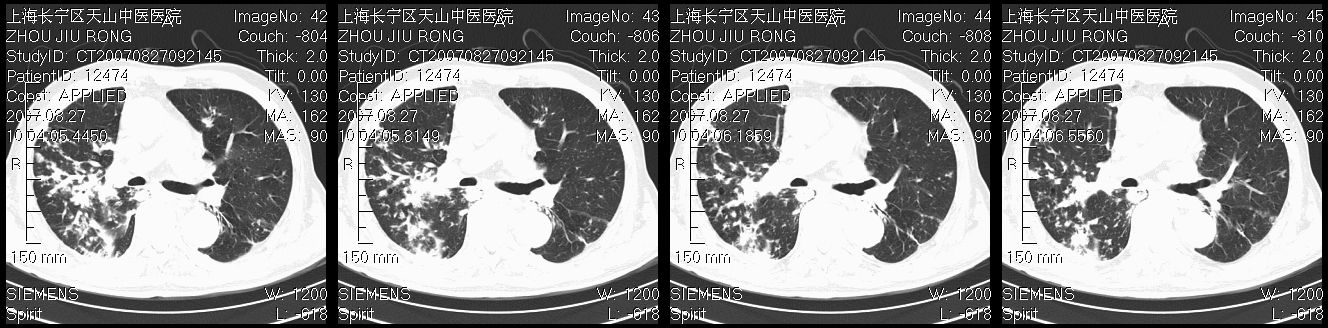

以下是引用zjzjr在2007-8-30 21:47:00的发言:[br]双肺弥漫性结节状、斑片状影,部分形成空洞,病灶以双肺上叶为著(符合结核发病部位),纵隔内见肿大淋巴结影。支持双肺继发性结核伴右上肺空洞形成。

以下是引用zjzjr在2007-8-30 21:47:00的发言:[br]双肺弥漫性结节状、斑片状影,部分形成空洞,病灶以双肺上叶为著(符合结核发病部位),纵隔内见肿大淋巴结影。支持双肺继发性结核伴右上肺空洞形成。

以下是引用gaoshengjiang在2007-8-31 10:24:00的发言:[br]双肺弥漫性斑片状影及多发空洞影,其间夹杂多量条索状影,胸膜肥厚、粘连并有结节状改变,纵隔多枚淋巴结肿大,考虑1双肺继发型肺结核合并感染?2韦格氏肉芽肿?[br] 支持!

以下是引用zjzjr在2007-8-30 21:47:00的发言:[br]双肺弥漫性结节状、斑片状影,部分形成空洞,病灶以双肺上叶为著(符合结核发病部位),纵隔内见肿大淋巴结影。支持双肺继发性结核伴右上肺空洞形成。

以下是引用zjzjr在2007-8-30 21:47:00的发言:[br]双肺弥漫性结节状、斑片状影,部分形成空洞,病灶以双肺上叶为著(符合结核发病部位),纵隔内见肿大淋巴结影。支持双肺继发性结核伴右上肺空洞形成。

以下是引用zjzjr在2007-8-30 21:47:00的发言:[br]双肺弥漫性结节状、斑片状影,部分形成空洞,病灶以双肺上叶为著(符合结核发病部位),纵隔内见肿大淋巴结影。支持双肺继发性结核伴右上肺空洞形成。